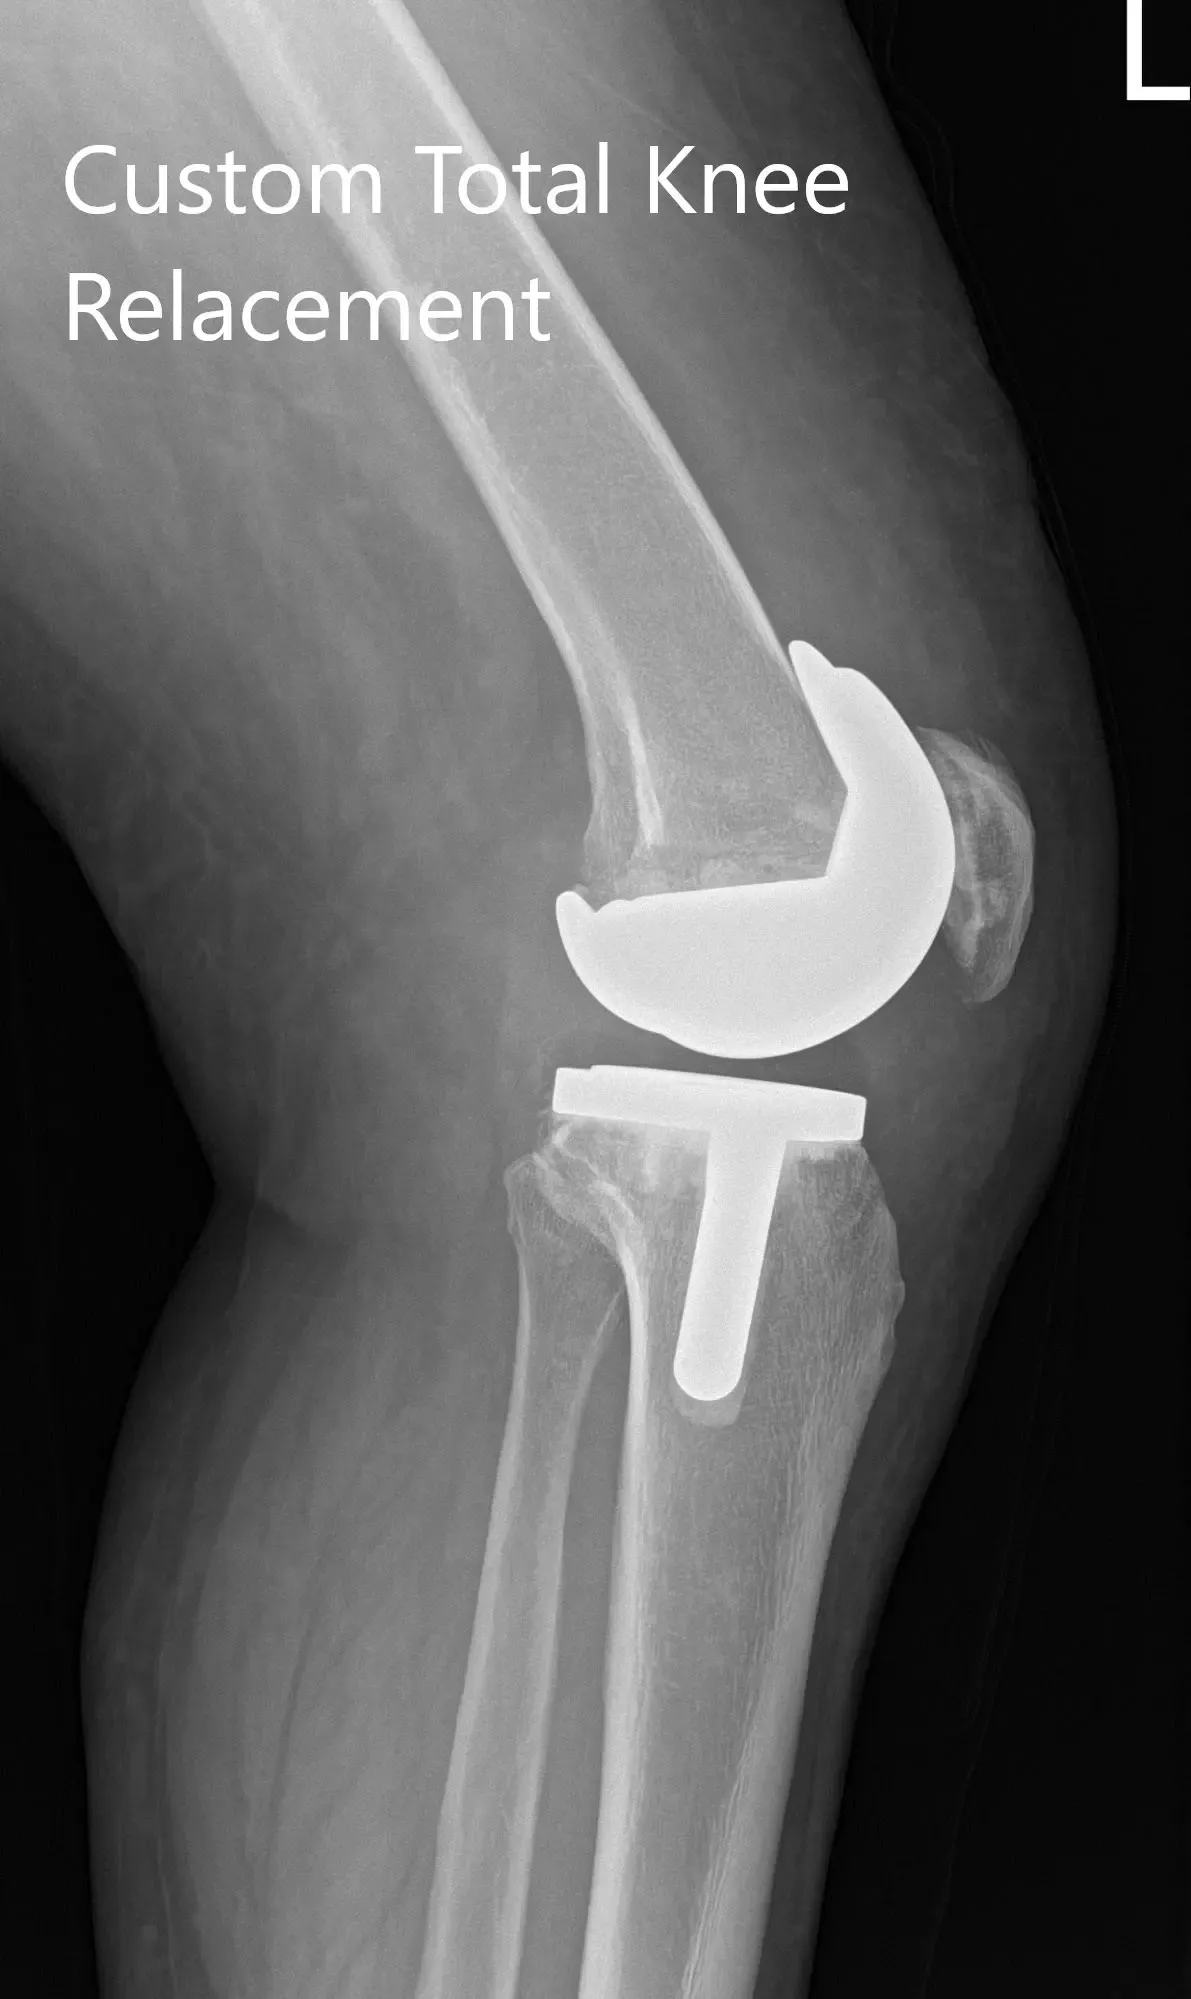

El paciente se sometió a una artroplastia total de rodilla izquierda utilizando el componente femoral personalizado con un componente tibial personalizado con una rótula de 32 mm y un inserto de polietileno de 8 mm.

Imágenes de radiografías postoperatorias que muestran la visión AP y lateral de la rodilla izquierda.